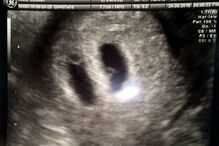

À medida que a gravidez de Jemma se foi desenvolvendo, nova ecografia mostrou que Jemma tinha dois sacos amnióticos: num deles desenvolvia-se um bebé e no outro estavam gémeos siameses.

Os gémeos estavam juntos na zona do peito e, por isso, partilhavam o mesmo coração, sistema respiratório e digestivo. O casal ficou destroçado quando lhe foram dadas as duas hipóteses que tinham: ou abortavam os gémeos siameses, ou perdiam os três bebés.